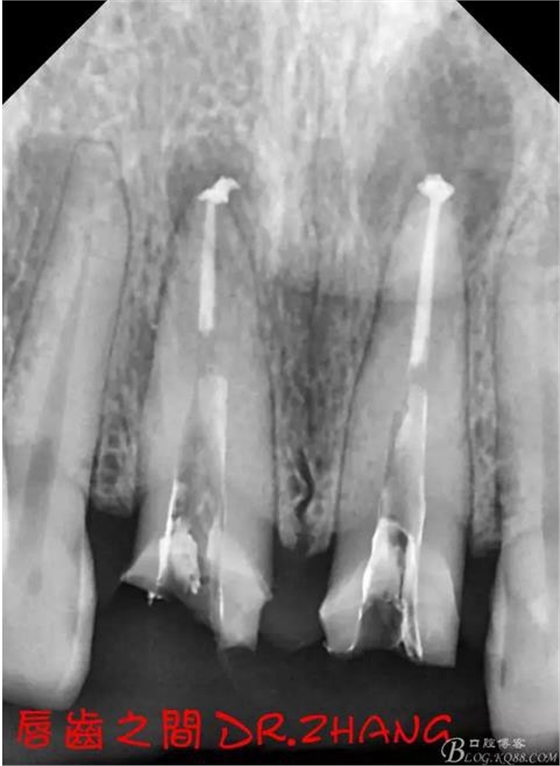

思博安熱牙膠系統(tǒng)根充 燙斷至根尖三分之一處后纖維樁恢復(fù)牙體組織

牙體預(yù)備后 硅橡膠取模 臨時牙恢復(fù)形態(tài)

復(fù)診:臨時牙良好 患者自訴無不適癥狀 去除臨時修復(fù)體 排齦 清理牙面 試戴全瓷修復(fù)體后粘結(jié) 常規(guī)醫(yī)囑 不適隨診